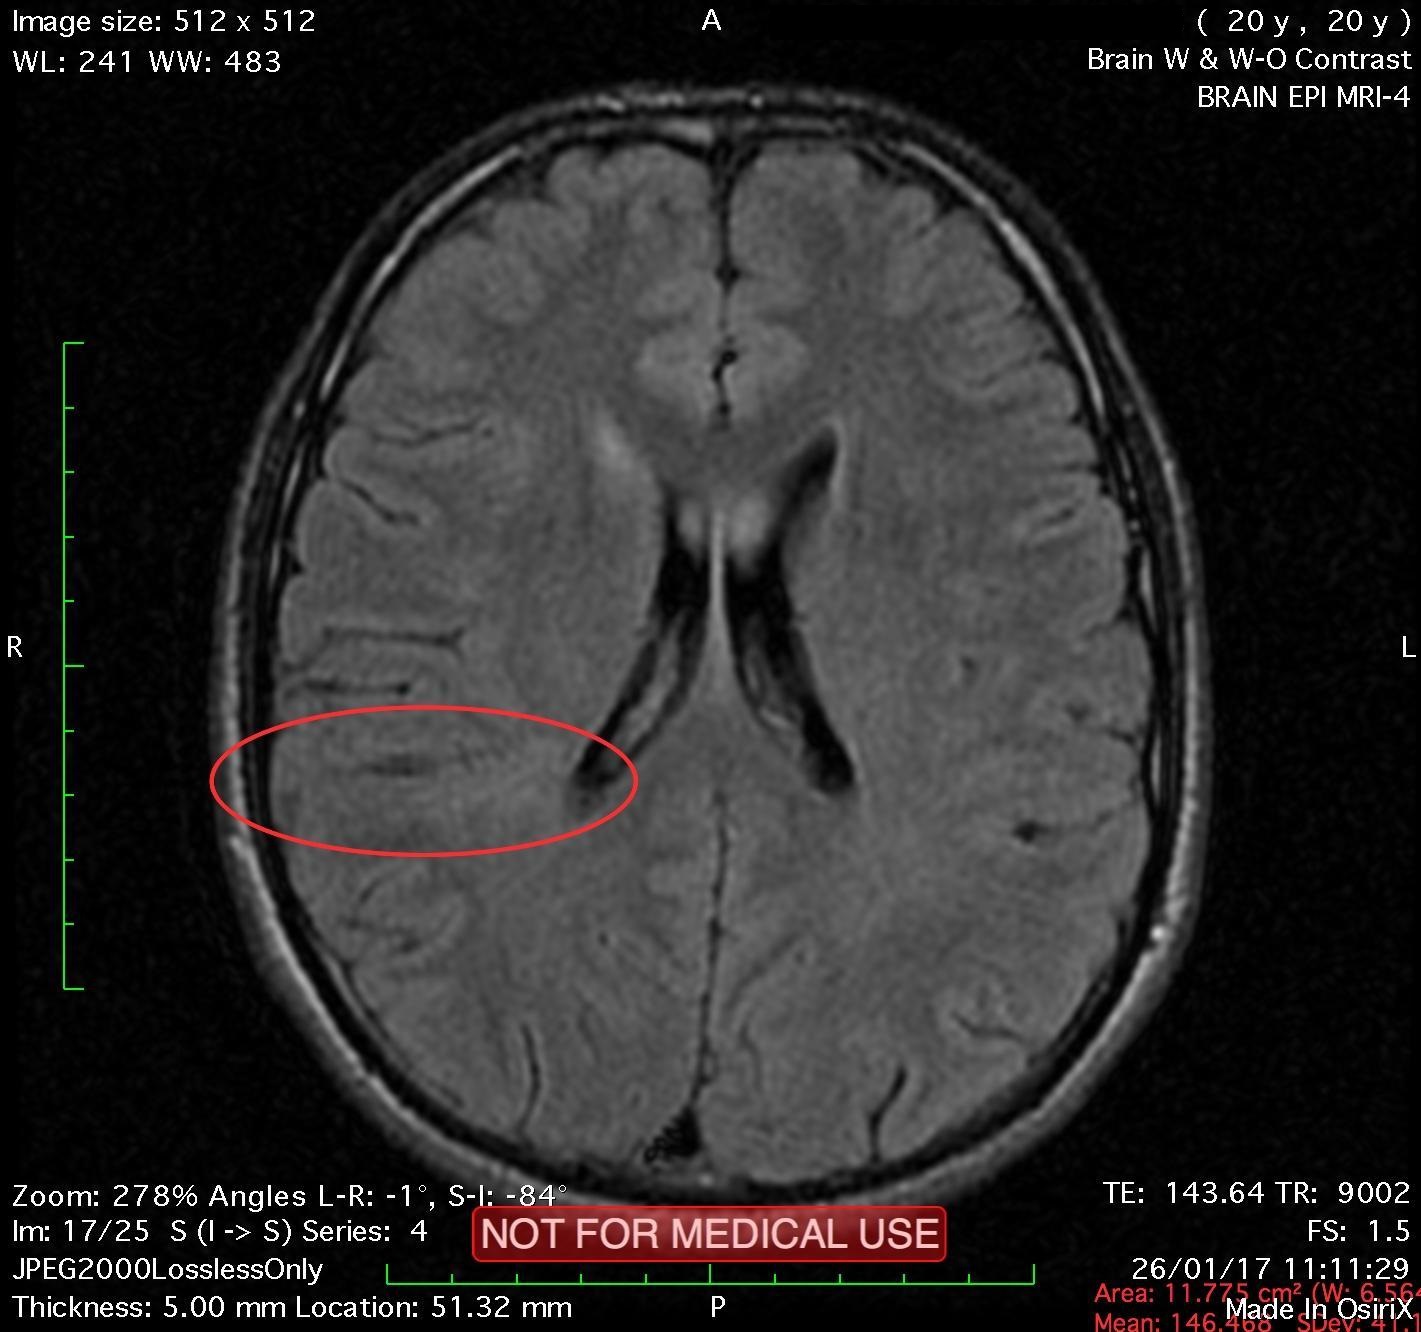

This recent MRI exam WITHOUT Contrast in IHC, revealed a subtle congenital malformation of cortical development within right parietal lobe.

A subtle linear band intensity extending between deep posterosuperior aspect of right Sylvian fissure and posterior aspect of corpus of right lateral ventricle (isointense with gray matter on all sequences). These MRI findings strongly suggest "Type II (Taylor type) focal cortical dysplasia (transmantle cortical dysplasia)" or "transmantle gray matter heterotopia". Virtually, they may be representing two different names for the same entity.

Secondary hippocampal sclerosis is identified, bilaterally (secondary to long-term intractable epilepsy).